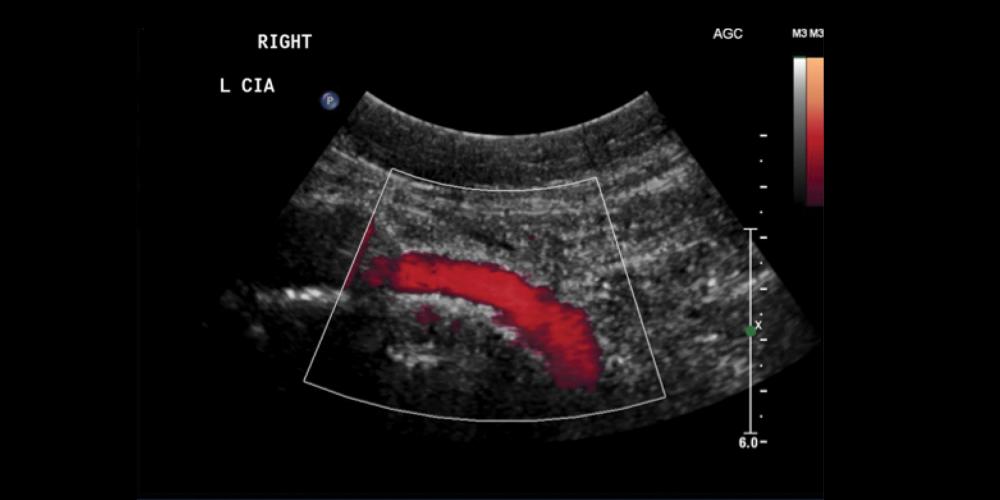

VBX Stent Graft flexibility and patency shown in discharge ultrasound